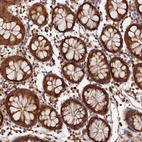

Immunohistochemical staining of human testis shows strong granular cytoplasmic positivity in cells in seminiferous ducts.